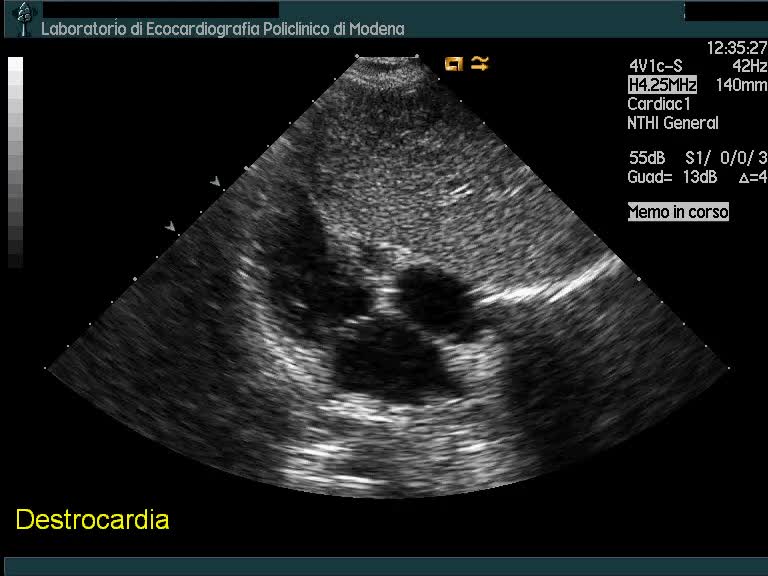

Titolo:

Destrocardia

Autore:

Andrea Barbieri